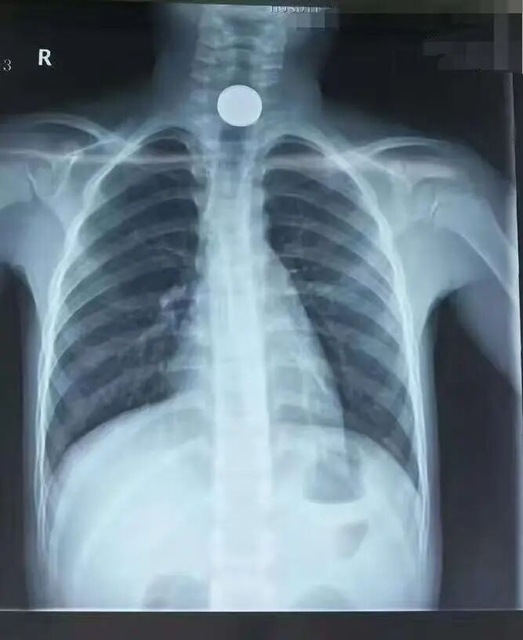

情况紧急,周兴玮立即安排孩子进行胸片检查。检查结果很快出来,提示食管第一狭窄处有一圆形高密度影,结合孩子误食硬币的病史,初步诊断为食管异物(硬币)。

原来,拍片时两枚硬币重叠在了一起,影像上只显示出一个高密度影;而手术过程中,由于食管松弛以及食管镜等器械的轻微推挤,另一枚硬币滑到了食管下方。